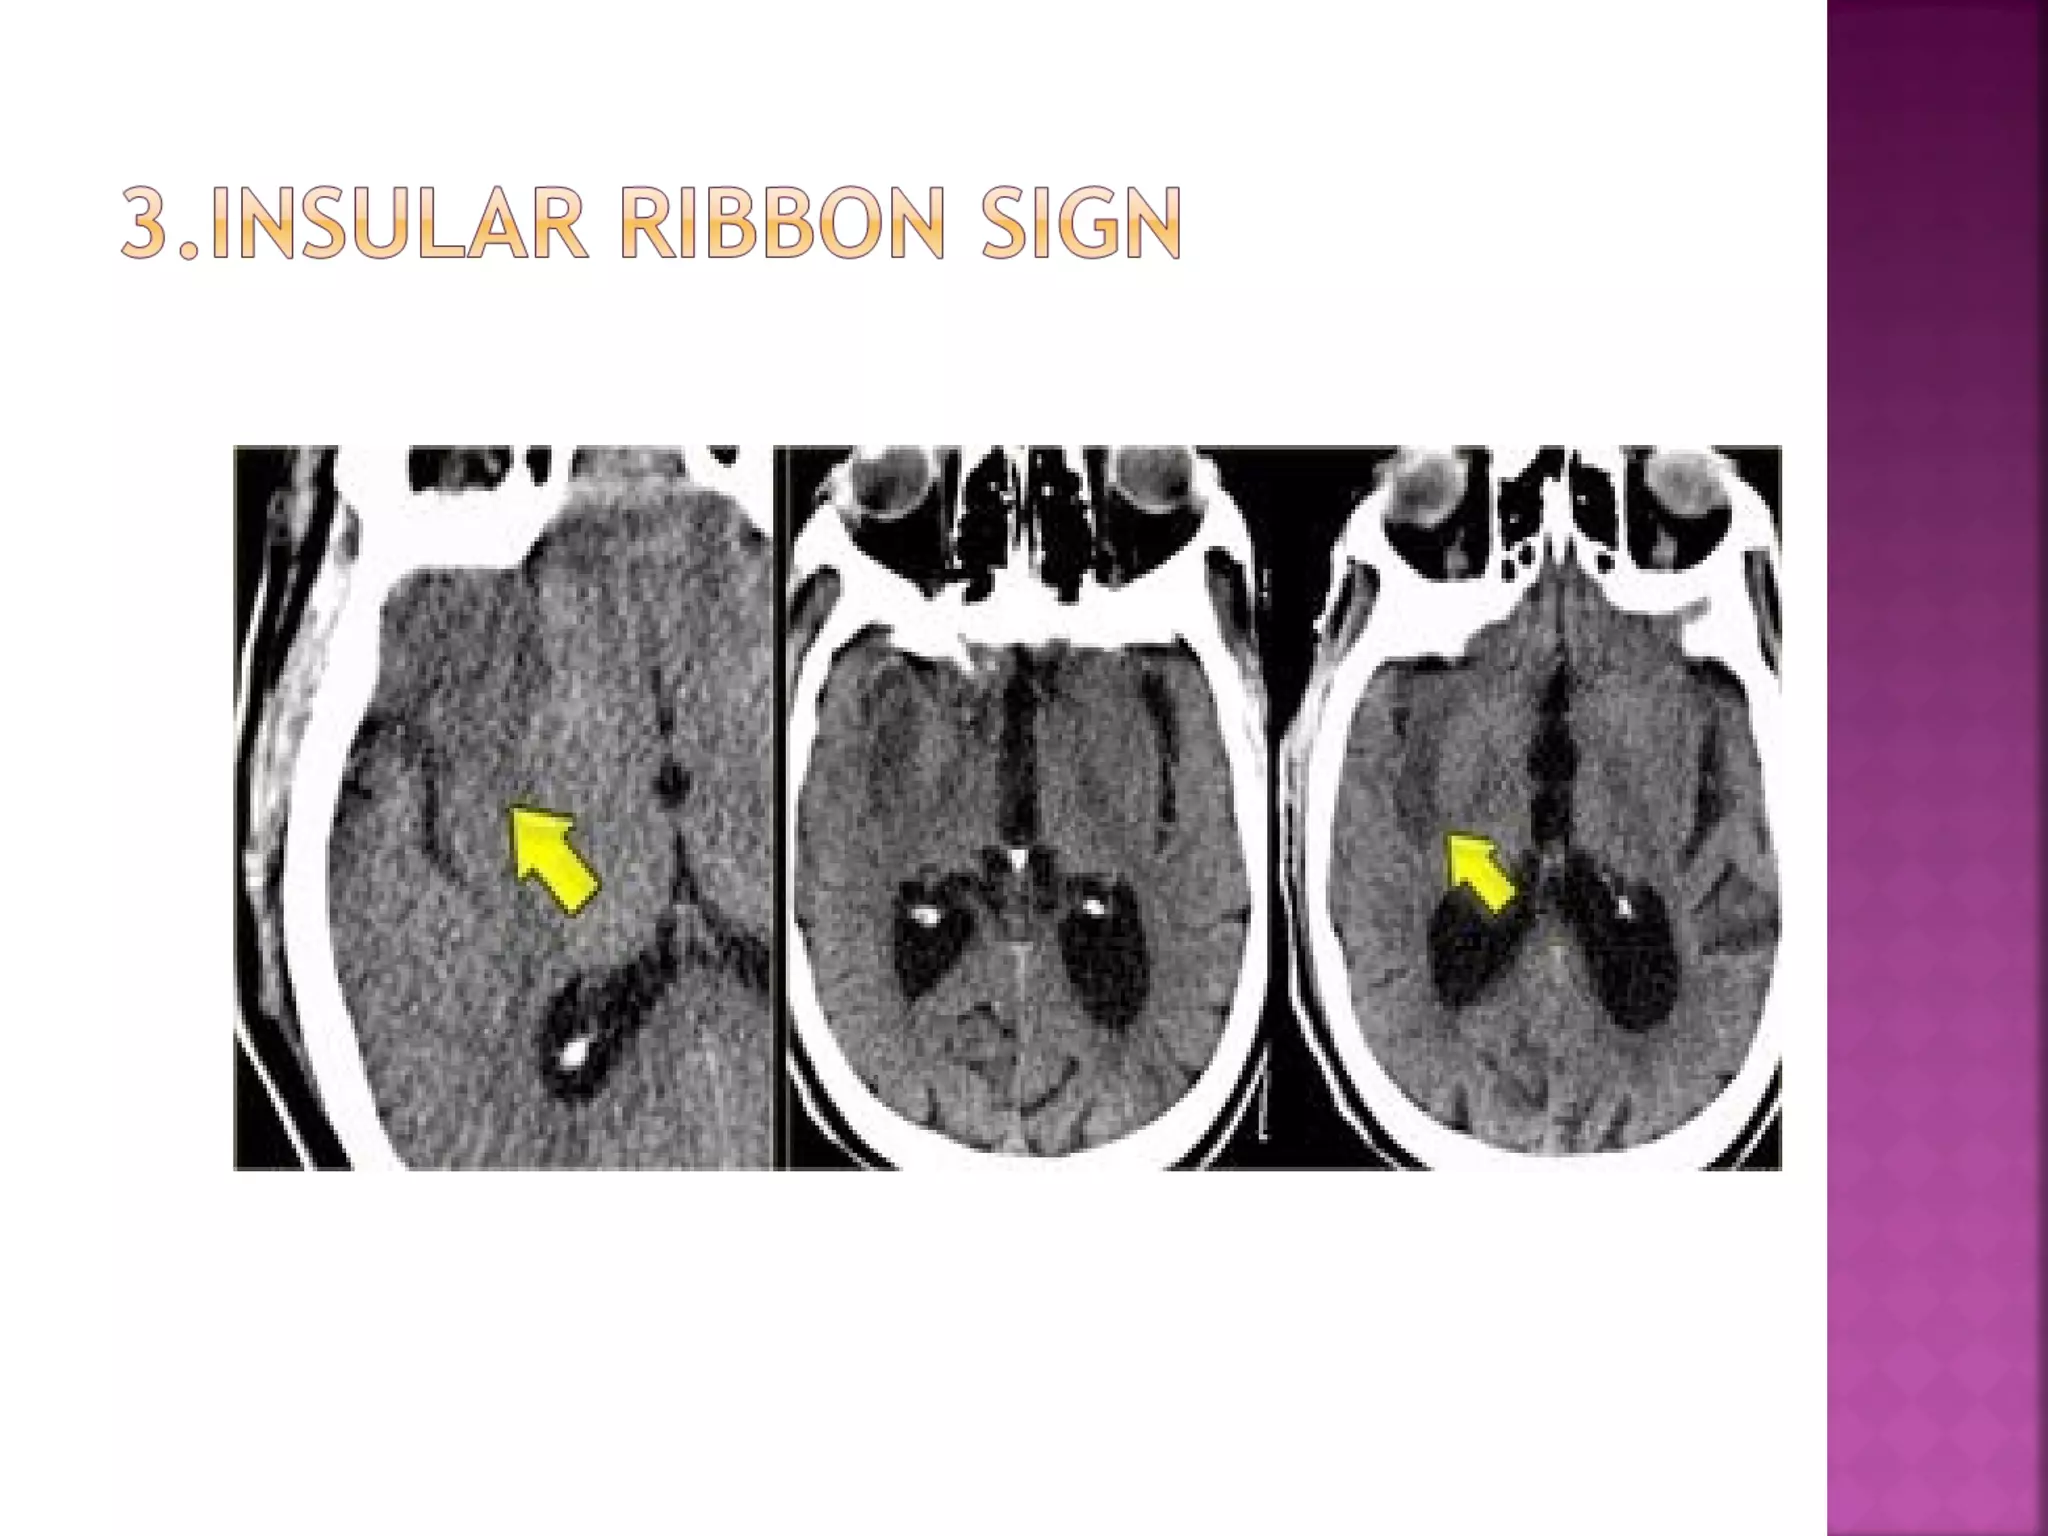

This refers to hypodensity and swelling of the

insular cortex.

It is a very indicative and subtle early CTsign of infarction in the territory of the

middle cerebral artery.

 This refers tohypodensity and swelling of the insular cortex. It is a very indicative and subtle early CTsign of infarction in the territory of the middle cerebral artery. It has to be differentiated from herpes encephalitis.